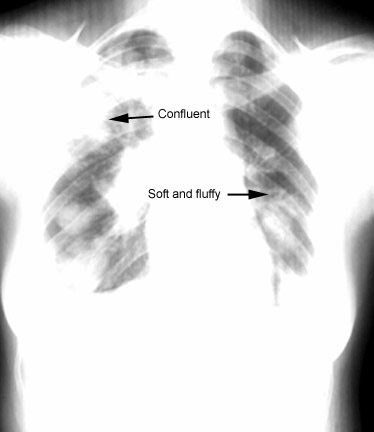

Soft fluffy edges

Distribution

Cortical

Eosinophilic pneumonia

BOOP

Lower lobes / Mineral oil aspiration